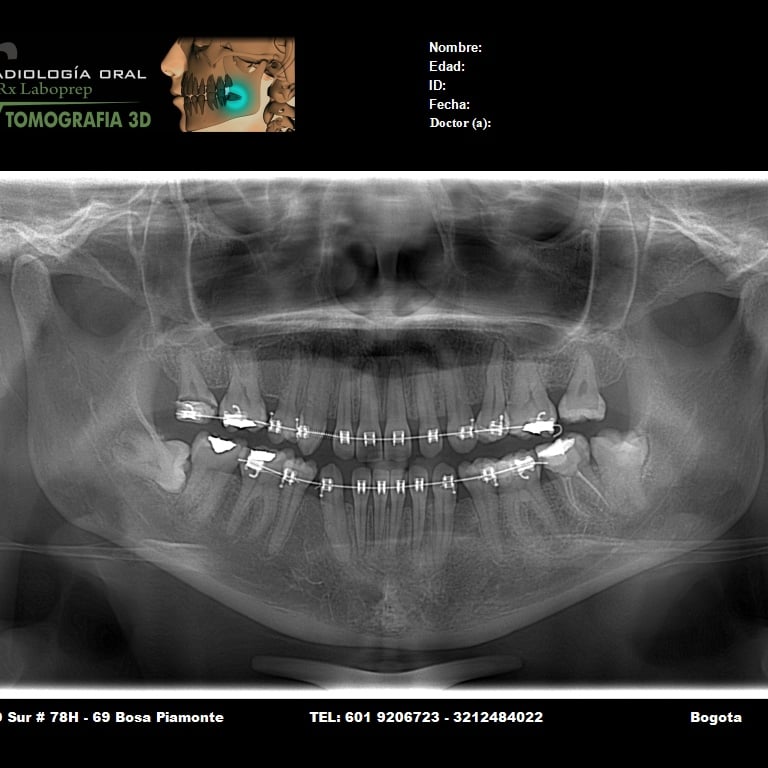

Galería

Imágenes de nuestros servicios radiológicos.